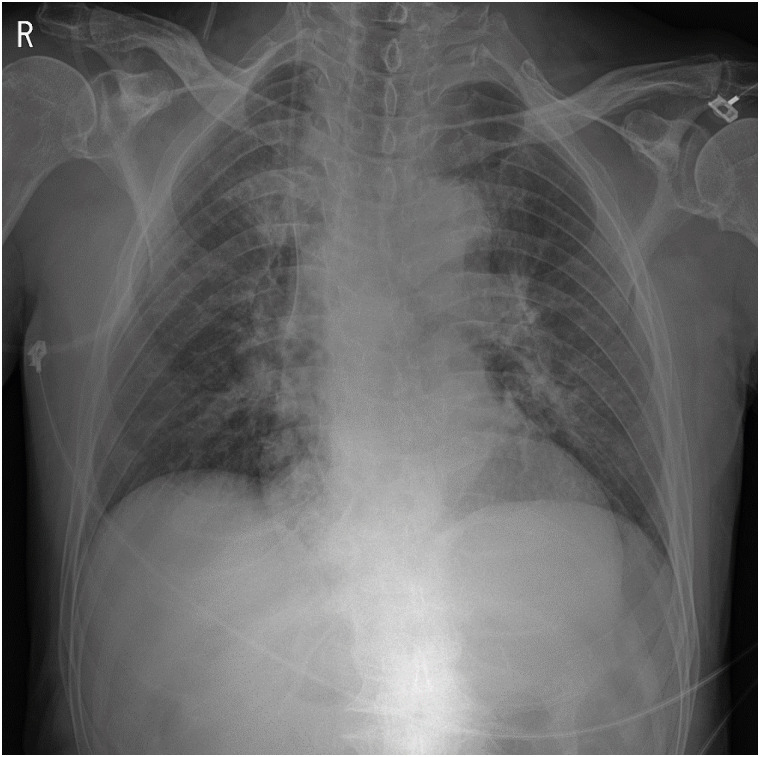

Fig. 2). A chest X-ray was taken at the time of the ED visit, and no pathological findings were observed (

Fig. 3 A chest X-ray. Anteroposterior view.

Systemic effect of glyphosate-containing herbicide poisoning via oral may induce kidney injury and pulmonary diseases such as pulmonary congestion or pneumonia [

18]. In case of skin absorption of herbicide insomuch as to induce systemic toxic effect, defects should have been noticed on lung as well as kidney. However, in this case, no pathological findings were seen in chest CT and chest X-ray views. Therefore, the possibility of direct multi-organ damages, such as kidney, lung, and heart, caused by HGlyGluS skin absorption seems relatively low.